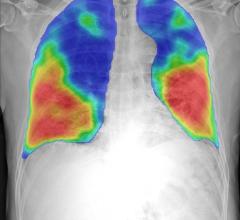

April 1, 2020 — Thirona and Delft Imaging launched CAD4COVID. This new artificial intelligence (AI) tool analyses X-ray ...